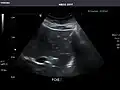

Ultrasonography of the liver with some standard measurements[6]

In patients with deranged liver function tests, ultrasound may show increased liver size (hepatomegaly), increased reflectiveness (which might, for example, indicate cholestasis), gallbladder or bile duct diseases, or a tumor in the liver.

Ultrasonography of liver tumors involves two stages: detection and characterization. Tumor detection is based on the performance of the method and should include morphometric information (three axes dimensions, volume) and topographic information (number, location specifying liver segment and lobe/lobes). The specification of these data is important for staging liver tumors and prognosis. Tumor characterization is a complex process based on a sum of criteria leading towards tumor nature definition. Often, other diagnostic procedures, especially interventional ones, are no longer necessary. Tumor characterization using the ultrasound method will be based on the following elements: consistency (solid, liquid, mixed), echogenicity, structure appearance (homogeneous or heterogeneous), delineation from adjacent liver parenchyma (capsular, imprecise), elasticity, posterior acoustic enhancement effect, the relation with neighboring organs or structures (displacement, invasion), vasculature (presence and characteristics on Doppler ultrasonography and contrast-enhanced ultrasound (CEUS).